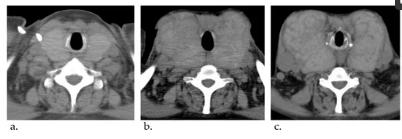

45岁时,依前列醇剂量增至32.5 ng/kg/min,但右心导管平均肺动脉压高至58 mmHg,控制不够。当时甲状腺肿大是轻微的(图1a)。因此医生进一步增加了依前列醇的剂量。经过16年的治疗,依前列醇维持在60-70 ng/kg/min,可以将其降至30 mmHg左右。虽然使用甲巯咪唑和左旋甲状腺素治疗Graves病控制了患者的甲状腺功能,但她的甲状腺肿大逐渐恶化(图1b)。54岁时,甲状腺检查显示TSH=3.33μIU/mL,游离T3=1.18 pg/mL,游离T4 = 3.06 pg/mL。然而,随着依前列醇的滴定,甲状腺肿进一步恶化(图1c)。

图一、甲状腺肿大的计算机断层成像过程。(a)45岁的时候。(b)52岁的时候。(c)54岁的时候。甲状腺逐渐增大